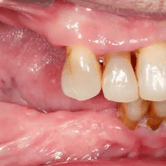

Pérdida de múltiples dientes

La pérdida de múltiples dientes es la ausencia de varios dientes que puede ser resultado de caries, enfermedades periodontales o traumatismos.

Los pacientes notan varios espacios vacíos en su boca, lo que afecta su capacidad para masticar y hablar adecuadamente.

El tratamiento incluye la colocación de varios implantes dentales para restaurar la función y la estética.